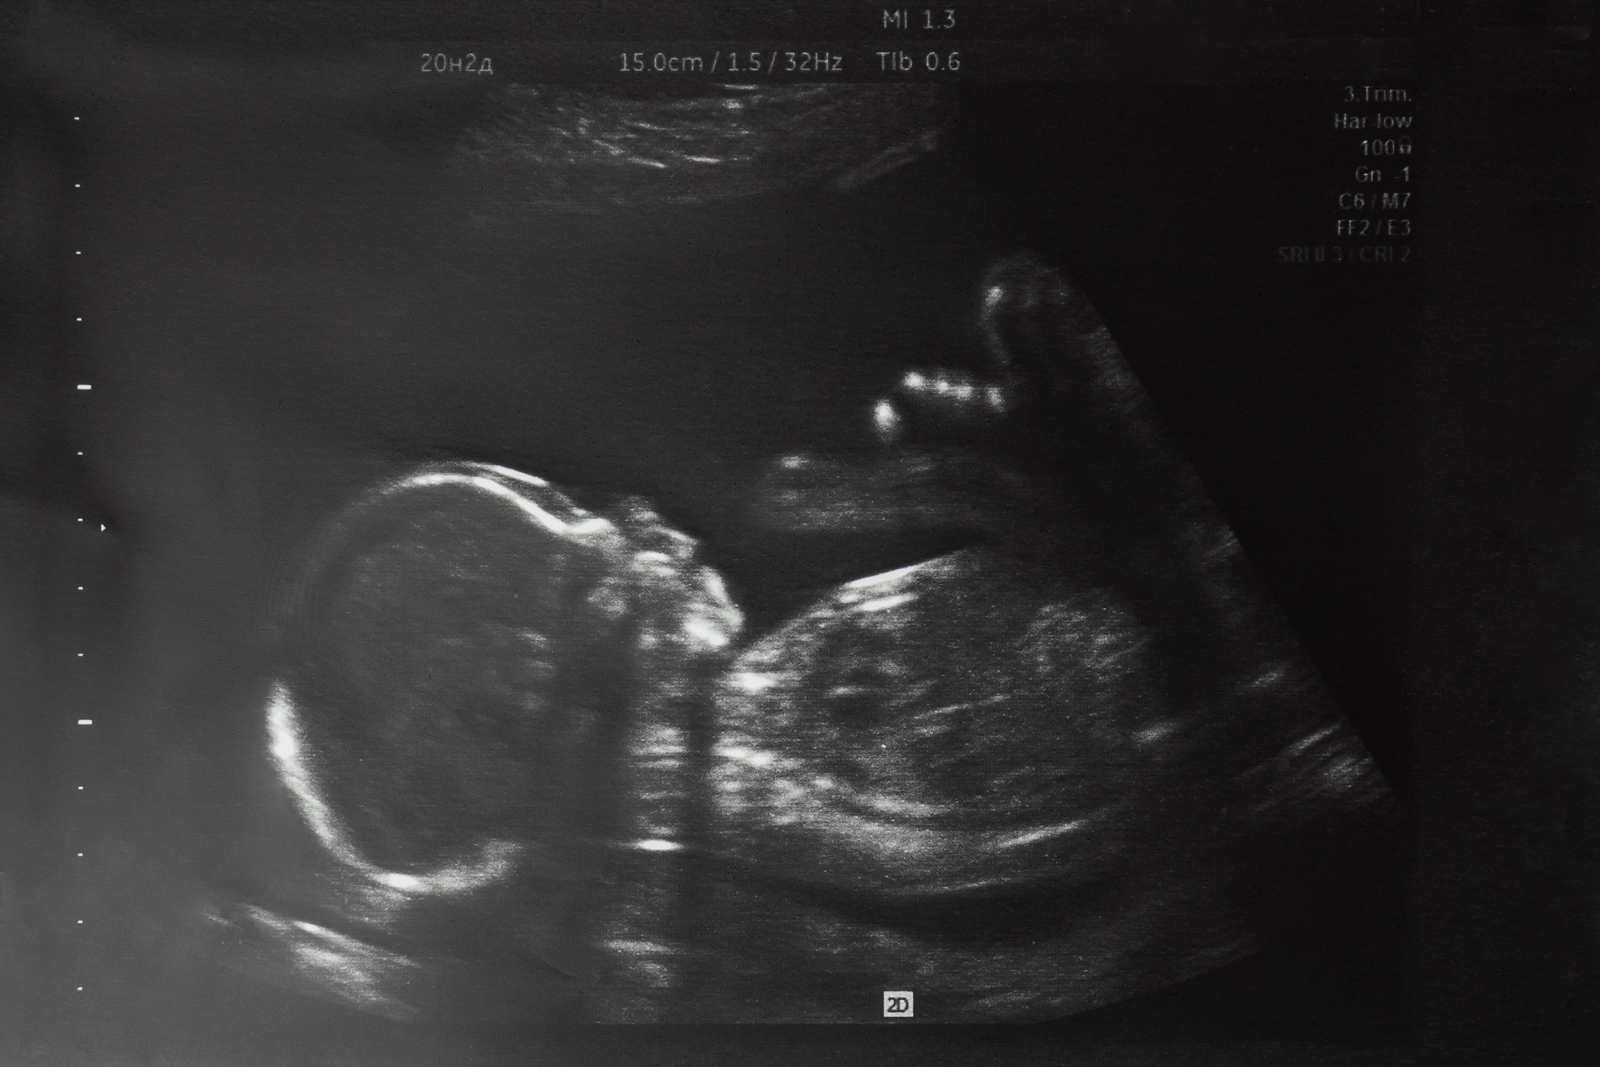

O caso da pré-adolescente catarinense de 11 anos que tinha engravidado depois de supostamente sofrer um estupro e, durante audiência que discutia a possível realização de um aborto, aceitara a proposta feita por uma promotora e uma juíza de prolongar a gestação até que o feto tivesse mais chances de sobrevivência, antecipando o parto e entregando o bebê para adoção, é uma prova de fogo para a sociedade brasileira. Não há como ficar indiferente ao drama desta menina e de sua família, nem aos esforços de duas profissionais do Direito para preservar ambas as vidas – esforços estes que comentamos neste espaço, na manhã desta quinta-feira. Este caso limítrofe, cujo desfecho ainda é desconhecido após intervenções da Defensoria Pública da União e de uma ala mais ideologizada do Ministério Público Federal (há relatos e desmentidos sobre uma suposta realização do aborto), serve para refletirmos qual o olhar dos brasileiros a respeito de um tema tão crucial quanto a defesa integral da vida humana em todas as suas fases.

Mas propomos também voltar o nosso olhar para o ser humano concebido como consequência da violência sexual. Será ele menos humano que uma criança concebida em um ato de amor, dentro de uma família sólida? Deve ele carregar a culpa pela monstruosidade alheia, pagando por ela com a própria vida? Não merece a chance de nascer e se desenvolver, seja junto de sua mãe biológica, seja com outra família disposta a acolhê-lo e amá-lo? Uma célebre campanha publicitária dos anos 90 trazia três corações praticamente idênticos, cada um com uma inscrição: “branco”, “negro” e “amarelo” (como sinônimo de “oriental”). A mensagem era inequívoca: somos todos iguais, todos dignos de respeito. Pois, da mesma forma, não há diferença ontológica alguma entre crianças no ventre de suas mães, independentemente da forma como foram concebidas. São todos seres humanos, indivíduos únicos, desde o momento do encontro dos gametas, diz-nos a biologia; e, nessa condição, têm direito inalienável à vida; são indefesos e inocentes, não agressores dos quais temos o direito de nos defender.